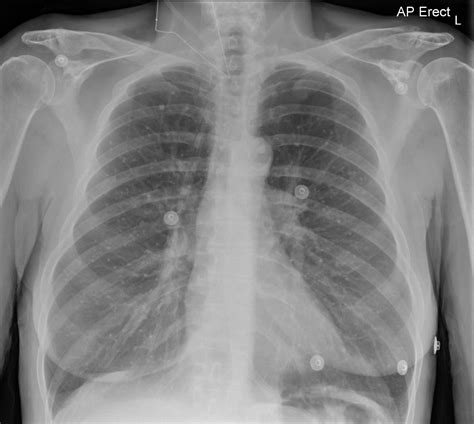

• Chest X-ray: A chest X-ray can reveal the presence of calcium deposits in the lungs.